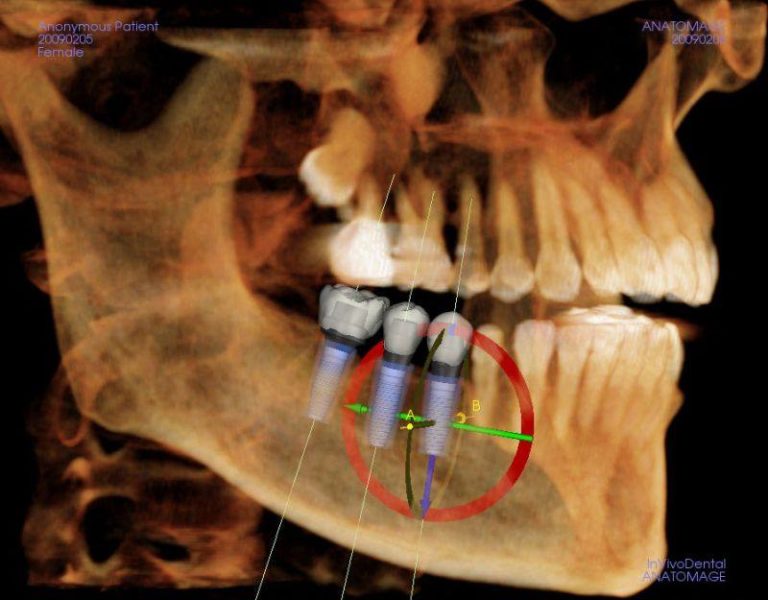

إذا سبق وأن تم أخذ طبعات أسنانك باستخدام صواني لزجة ومعجون، فمن المحتمل أنك تتذكر مدى عدم الراحة التي قد تسببها. الخبر السار؟ أن العديد من عيادات الأسنان تستخدم الآن بديلاً حديثاً ومريحاً يُسمى الماسح الضوئي الفموي. الماسح الضوئي الفموي هو كاميرا صغيرة محمولة باليد يستخدمها طبيب الأسنان لالتقاط صور رقمية ثلاثية الأبعاد لأسنانك — بدون معجون، بدون صواني، وبدون الشعور بالغثيان.